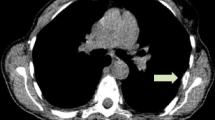

Imaging Results

Imaging examples from two patients are provided (Fig. 1). Both patients had lymph node metastases from ER+ breast cancer. Patient A (15-002) whose axillary mass biopsy demonstrated ER positivity had high FES uptake at each site identified on FDG-PET. Patient B (3-001) whose T10 vertebral lesion tumor biopsy was ER- had nodal metastases clearly visualized on FDG-PET, but not appreciated by FES-PET.

Imaging examples from two patients who underwent both FES and FDG scans prior to therapy. Left panel: Patient A (15-002) had mediastinal lesions appreciated by both FES and FDG. Right panel: Patient B (3-001) also had mediastinal disease clearly seen by FDG-PET, not visible on FES-PET. The core biopsy of a metastatic axillary lesion from Patient A showed ER + breast cancer, while the needle biopsy of a vertebral lesion from Patient B showed ER- breast cancer.